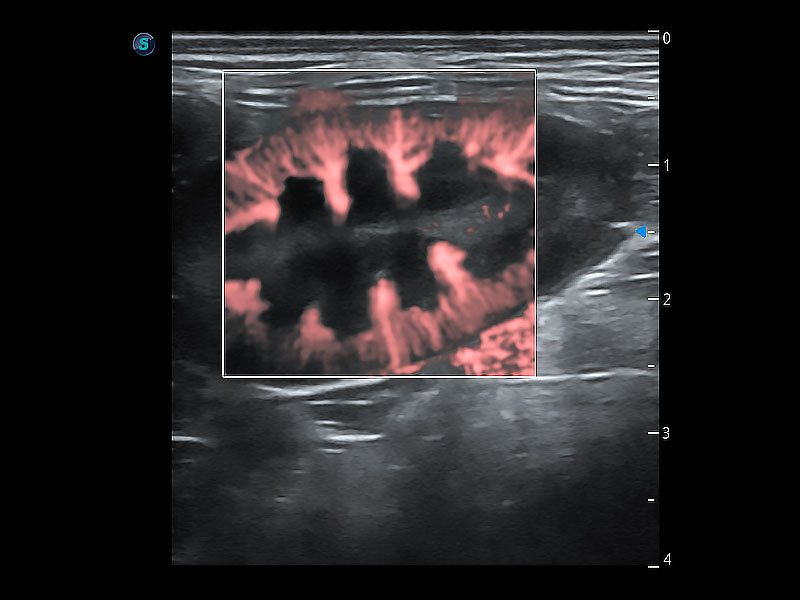

• Micro F 显微血流成像

极大提升超低速微细血流的检出能力,同时更精准地滤除软组织和超声信号,为兽用医生提供以往无法通过常规血流获得的疾病诊断信息。

ProPet 80 全新的动物超声智能软件和丰富的探头群,为动物医生提供了高清晰度和精细分辨率的图像,无论在宠物、马科、畜牧还是实验室动物等应用中都可以轻松应对,为您的日常工作带来满意的体验。

(犬)肾脏显微血流